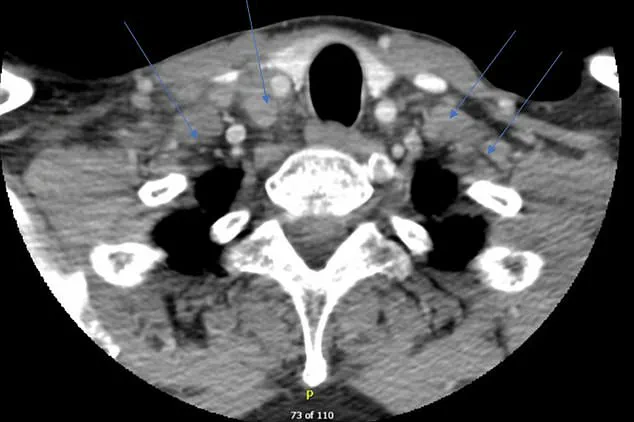

Following an initial period without noticeable issues, the patient’s symptoms began to resurface six months after beginning his medication regimen for arthritis. Complaints of headaches, night sweats, fever, and swollen lymph nodes in his neck prompted further investigation. A CT scan revealed inflamed lymph nodes on both sides of his neck.

Imaging diagnostics such as CT scans provided crucial insights into the extent of lymph node swelling, with images showing enlarged lymph nodes on both sides of the neck. This visual confirmation helped doctors tailor their approach to managing the patient’s condition effectively.